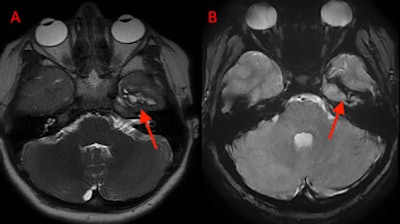

On hospital day two, follow-up magnetic resonance imaging (MRI) two showed a stable intraparenchymal hematoma and no evidence of infection. On hospital day four, the patient's pain was well controlled with acetaminophen, and the boy reported no nausea or vomiting. At this time, he was discharged with a walker to assist with walking, they wrote.

(A) Axial MRI with contrast shows residual hematoma within the temporal lobe two days after removal. (B) Coronal MRI without contrast also shows temporal lobe hematoma.